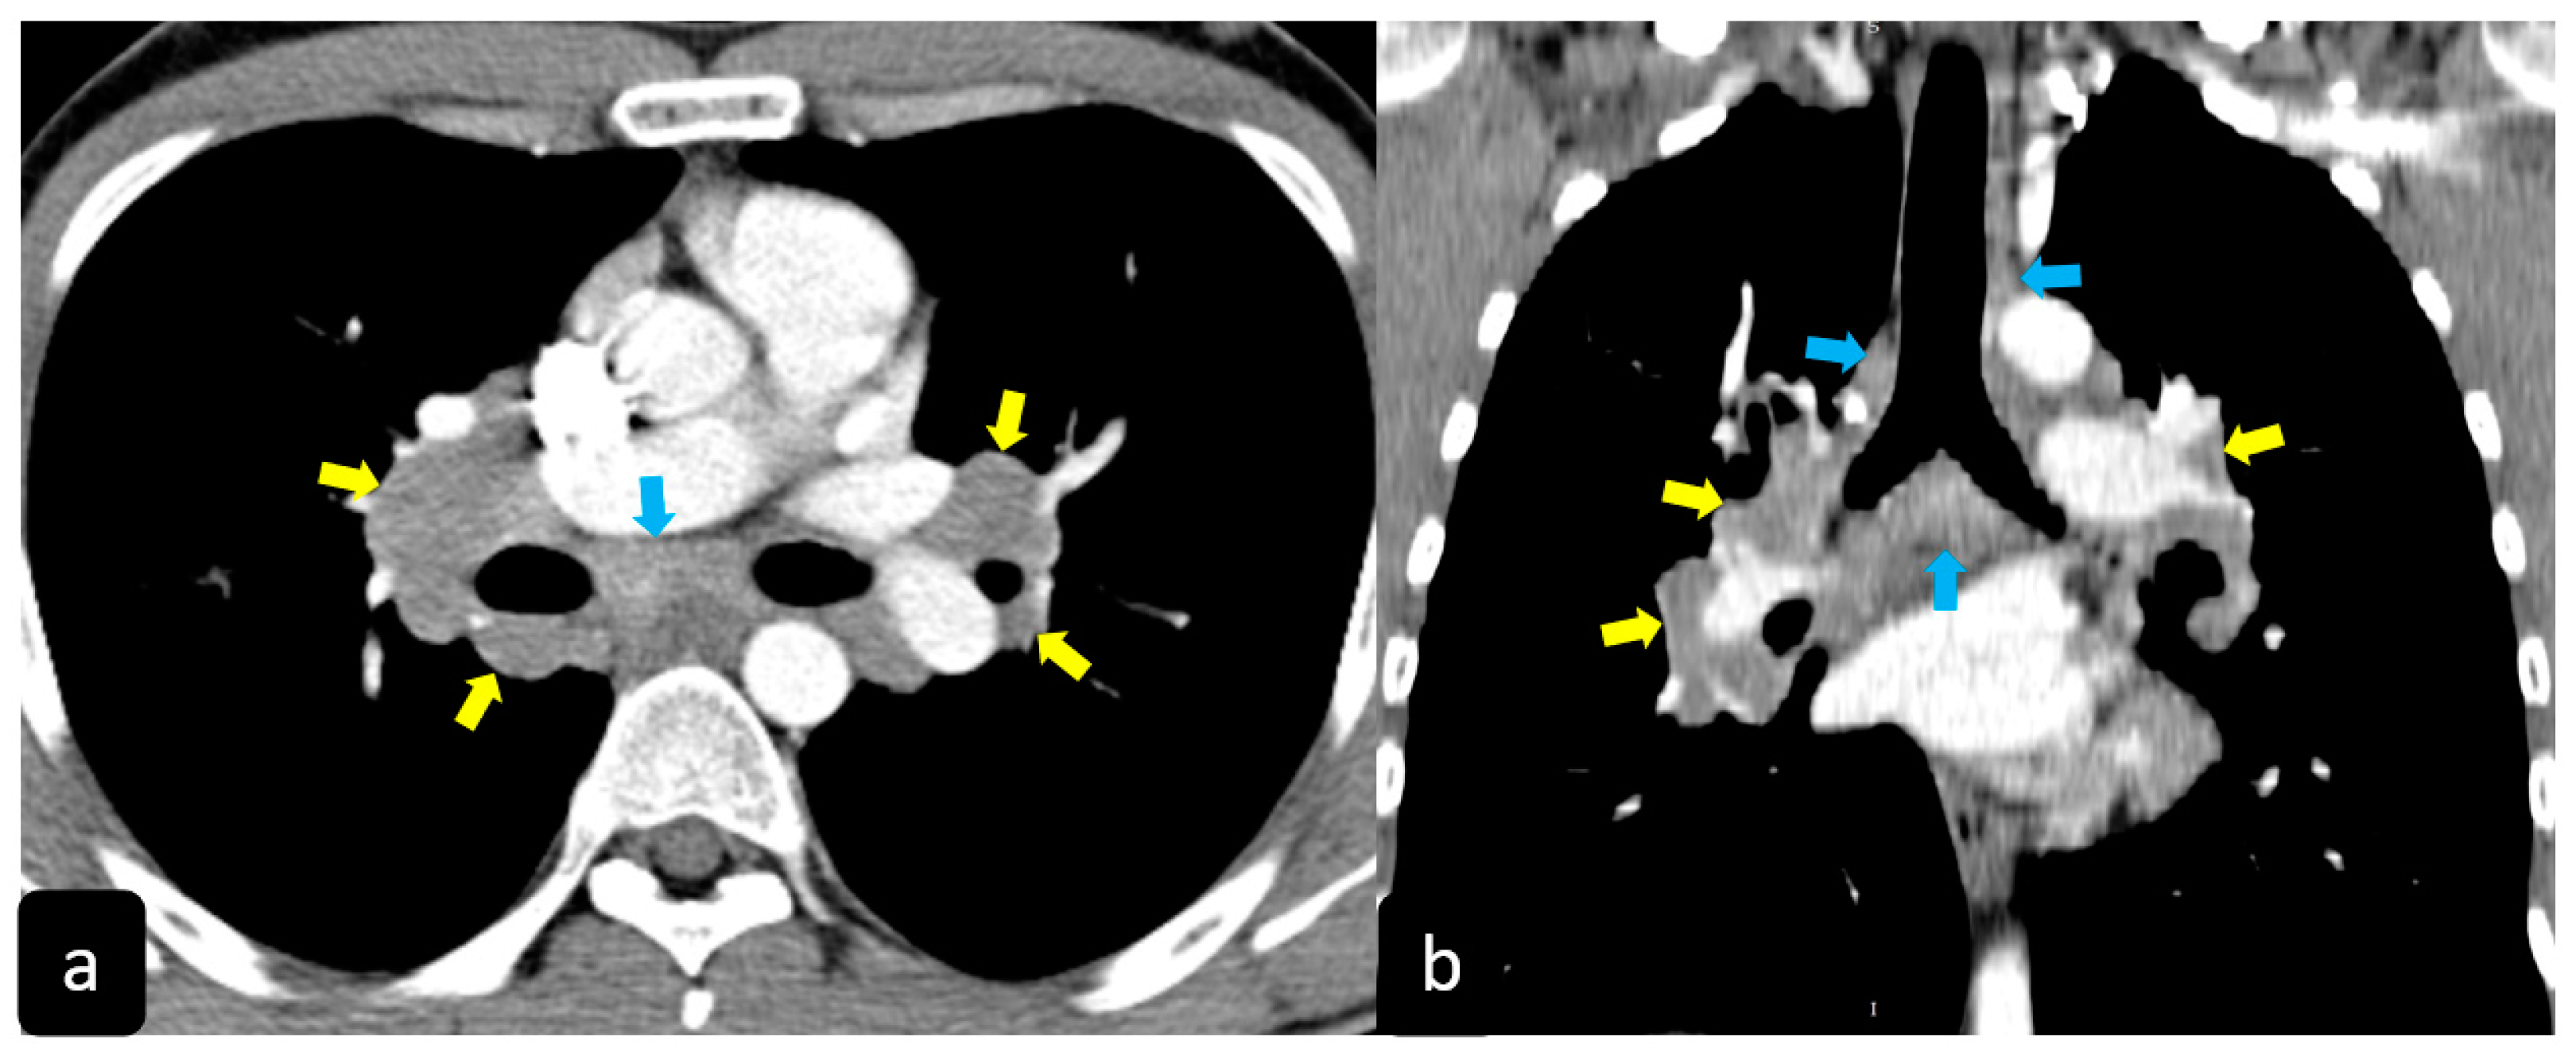

2.2. Typical and Atypical Manifestation of Pulmonary Sarcoidosis at HRCT

- Tana, C.; Donatiello, I.; Coppola, M.G.; Ricci, F.; Maccarone, M.T.; Ciarambino, T.; Cipollone, F.; Giamberardino, M.A. CT Findings in Pulmonary and Abdominal Sarcoidosis. Implications for Diagnosis and Classification. J. Clin. Med. 2020, 9, 3028. [Google Scholar] [CrossRef] [PubMed]